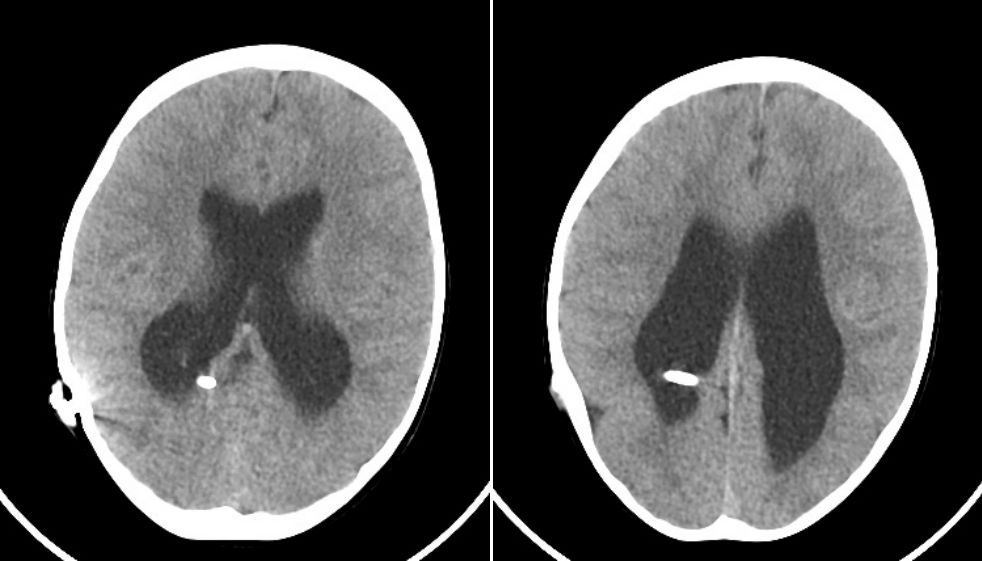

术后2年半(2015.7.12)复查CT:脑室形态较前好转缩小,脑实质发育良好。

术后4年(2016.12.29)复查CT如下:同前相仿。

术后1年半(2014.5.16)复查CT:脑室形态较前好转缩小,脑实质发育良好。

术后2年半(2015.7.23)复查CT:较前相仿。

术后4年复查(2016.12.29)CT:较前相仿。